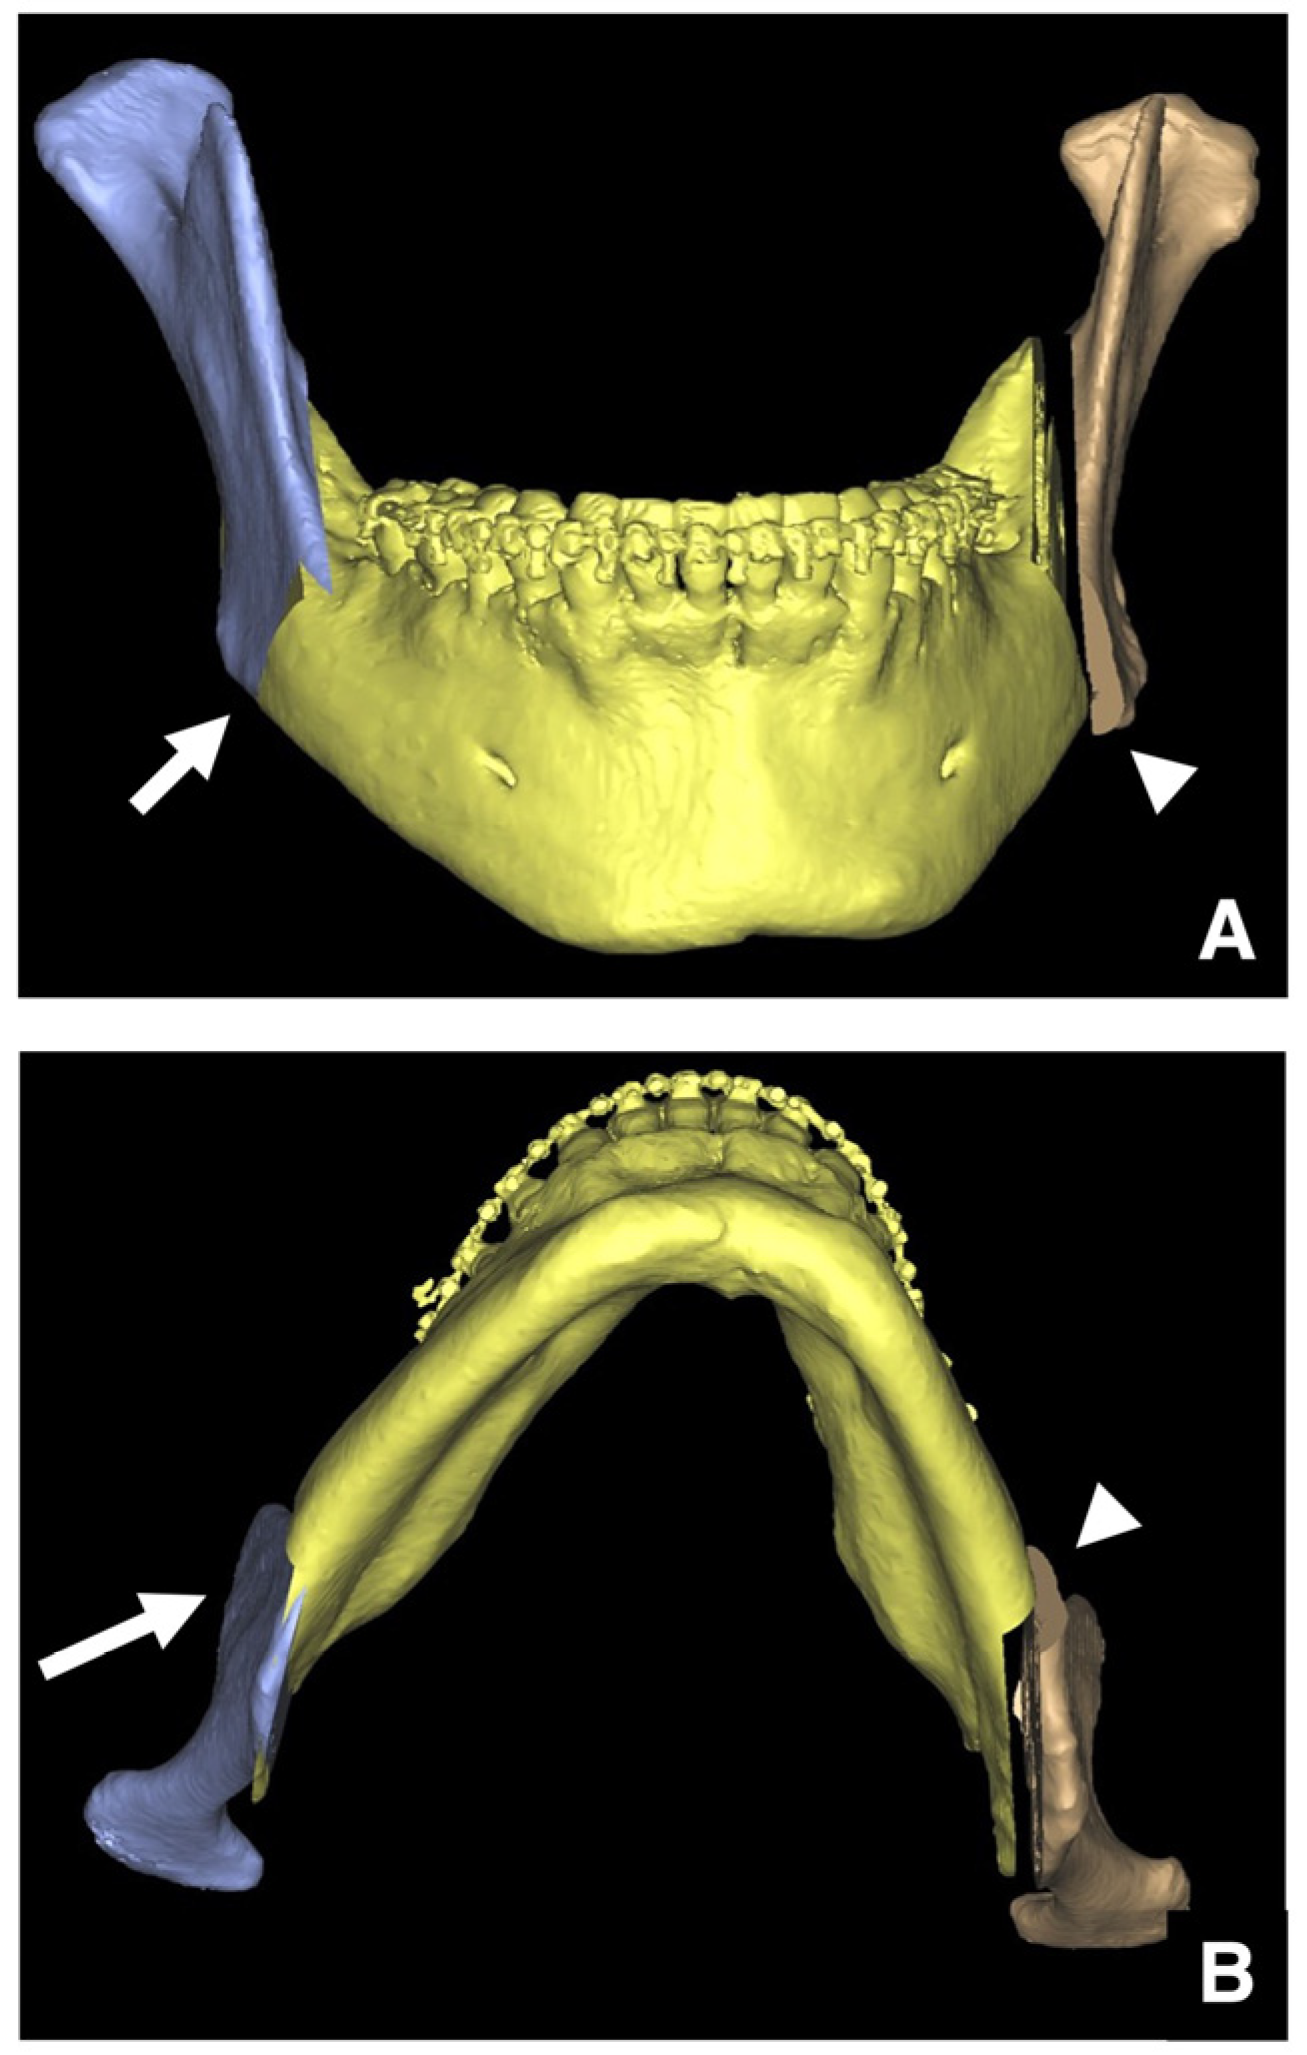

| Setting the osteotomy line 1. Evaluation of the position of the mandibular canal and surrounding bone quality Presence or absence of mandibular canal bifurcation and course of resection site Distance from the buccal wall of the mandibular canal to the buccal cortical bone margin Bone quality around the mandibular canal (CT number) 2. Distance from the mandibular notch to the lingula Whether it is 14 mm or more 3. Morphology of the mandible and variation in cortical bone thickness Cortical bone thickness in the medial osteotomy area and lateral osteotomy area Enhanced safety through improved visibility 1. Medial curvature of the mandibular ramus Mandibular ramus is straight or strong curvature 2. Course of small blood vessels along the bone surface Depression of the buccal-lingual cortical bone from the mandibular fossa to the mandibular ramus region, trabecular bone defect Improved success rates through enhanced postoperative bone integration 1. Degree of interference between bone segments The presence or absence of interference between the proximal and distal bone segments formed during virtual mandibular deformity surgery |